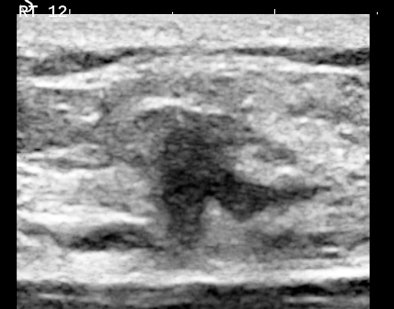

Figures 3A and 3B are the B-mode and simultaneous SWE of a follicular neoplasm of the thyroid. Notice how the elastogram indicates a cell population heterogeneity that is not visible in the original image.

![]() |

| Figures 3A and 3B. |

Homogeneous and heterogeneous are classic ultrasound image features. Perhaps ultimately, refining this descriptor and even quantifying it will be the most important role of SWE in practice.